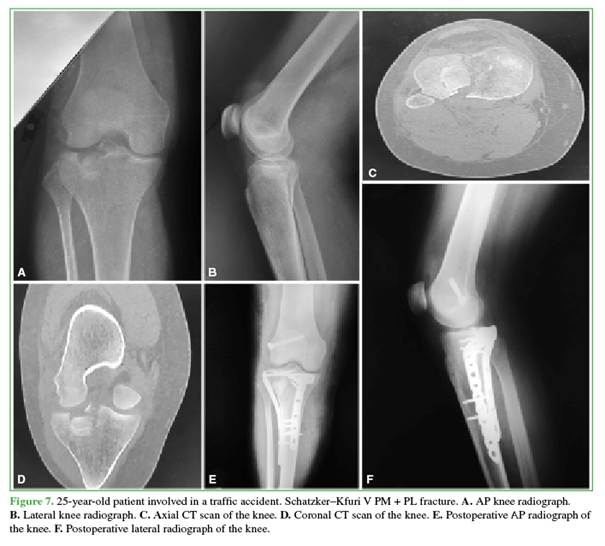

Condylar width, the medial proximal tibial angle, and tibial slope were measured and compared with the contralateral knee, all of which fell within normal parameters. All patients had <2 mm of articular depression, except for one patient with a 3-mm depression. No cases of nonunion or displacement of the epicondylar osteotomy bone block were observed (Figures 7 and 8).